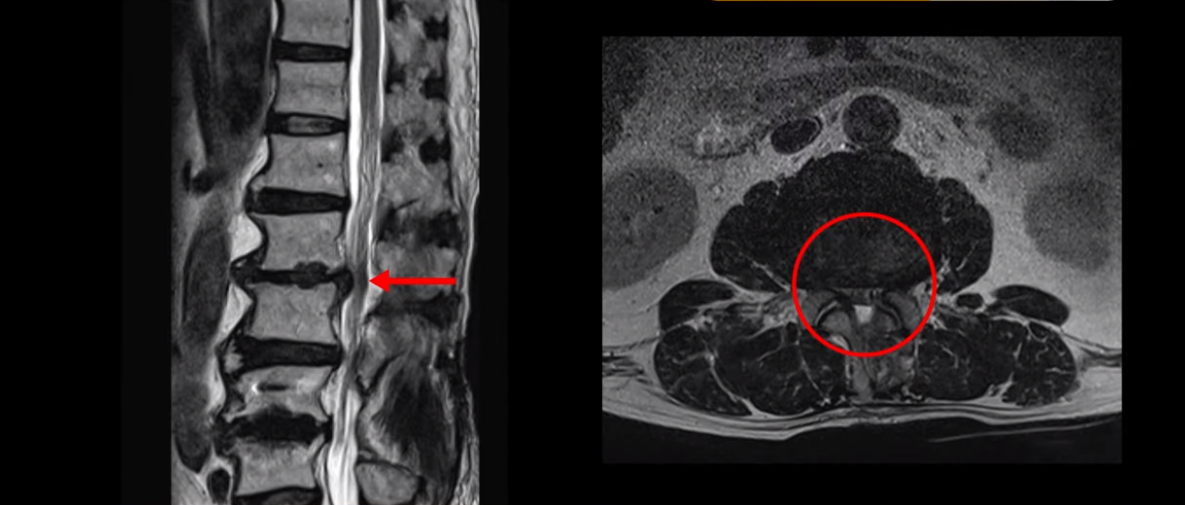

이분 허리 MRI를 보면서 간단히 설명드린 후 유합술 이후 인접마디에 문제가 생긴 환자분들이 왜 추가적인 수술을 서두르기보다는 허리기능을 살려주는 근육신경재활치료를 받는 게 좋은지, 또 치료는 어떻게 하는 게 좋은지 자세히 설명드리겠습니다. 이분 MRI를 보면 4번 5번에 나사가 박혀있습니다.

이렇게 나사가 박혀있으면 그 위나 아래에 문제가 많이 생기고 그걸 인접분절질환이라고 부릅니다. 이분도 유합술을 받은 그 윗마디인 2번 3번에서 디스크가 터져 밀려나와서 수술을 받았는데

이게 수술 후 사진인데도 여전히 척추관은 좁습니다.

나사 박은 마디 위쪽에 수술을 받았지만 수술 후에도 전혀 통증이 좋아지지 않고 다리에 힘도 빠져서 워커를 잡고 겨우 걷는 상태였습니다. 이렇게 유합술 이후 그 위나 아래에 문제가 생기는 인접분절질환은 모든 척추질환 중 가장 치료가 어려운 질환 중 하나로 꼽힙니다.

척추에 유합술을 해서 허리의 기능, 특히 근육의 기능이 많이 떨어진 환자들은 허리의 기능이 많이 떨어질수록 추가적인 수술을 해도 또다시 통증을 겪을 가능성이 높아집니다. 이런 통증을 척추수술 후 실패증후군, 또는 척추수술 후 통증증후군이라고 부릅니다. 허리의 기능이 많이 떨어질수록 수술로 신경 눌린 것을 잘 풀어줘도 여전히 아플 수가 있습니다. 이분도 역시 수술한 부분 위에서 디스크가 터졌다고 해서 수술을 받으셨는데 수술 후에도 통증은 똑같이 남아있습니다. 수술한 의사는 수술이 잘 됐다고 왜 아픈지 모르겠다고 하니까 환자만 답답한 겁니다.